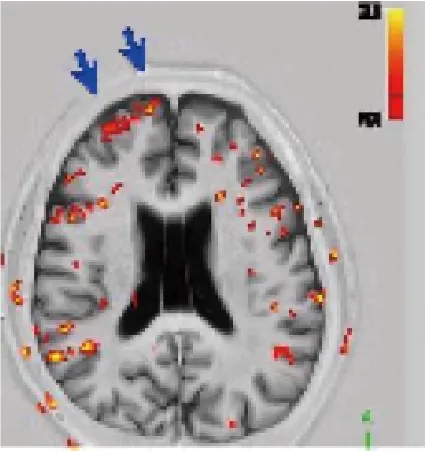

近赤外線誘発機能的MRI検査

低出力近赤外線照射誘発機能的fMRI検査で、前頭葉機能の評価と、前頭葉賦活法を行います。基本的に保険診療の頭部MRIの適応の範囲内で行う検査です。高磁場MRI室に設置した810 nm CW diode laser装置をもとにして、非磁性体で作成した7mの光ファイバーを通して、被験者の前額部に近赤外線を照射し、照射前、照射中の信号変化を測定しfMRIを撮像します(下図)。近赤外線は温熱効果が少なく、米国FDAとANSIで定められた安全基準の320 mW/cm2より、はるかに少ないエネルギー密度で照射し、皮膚の熱感も起こさないレベルです。